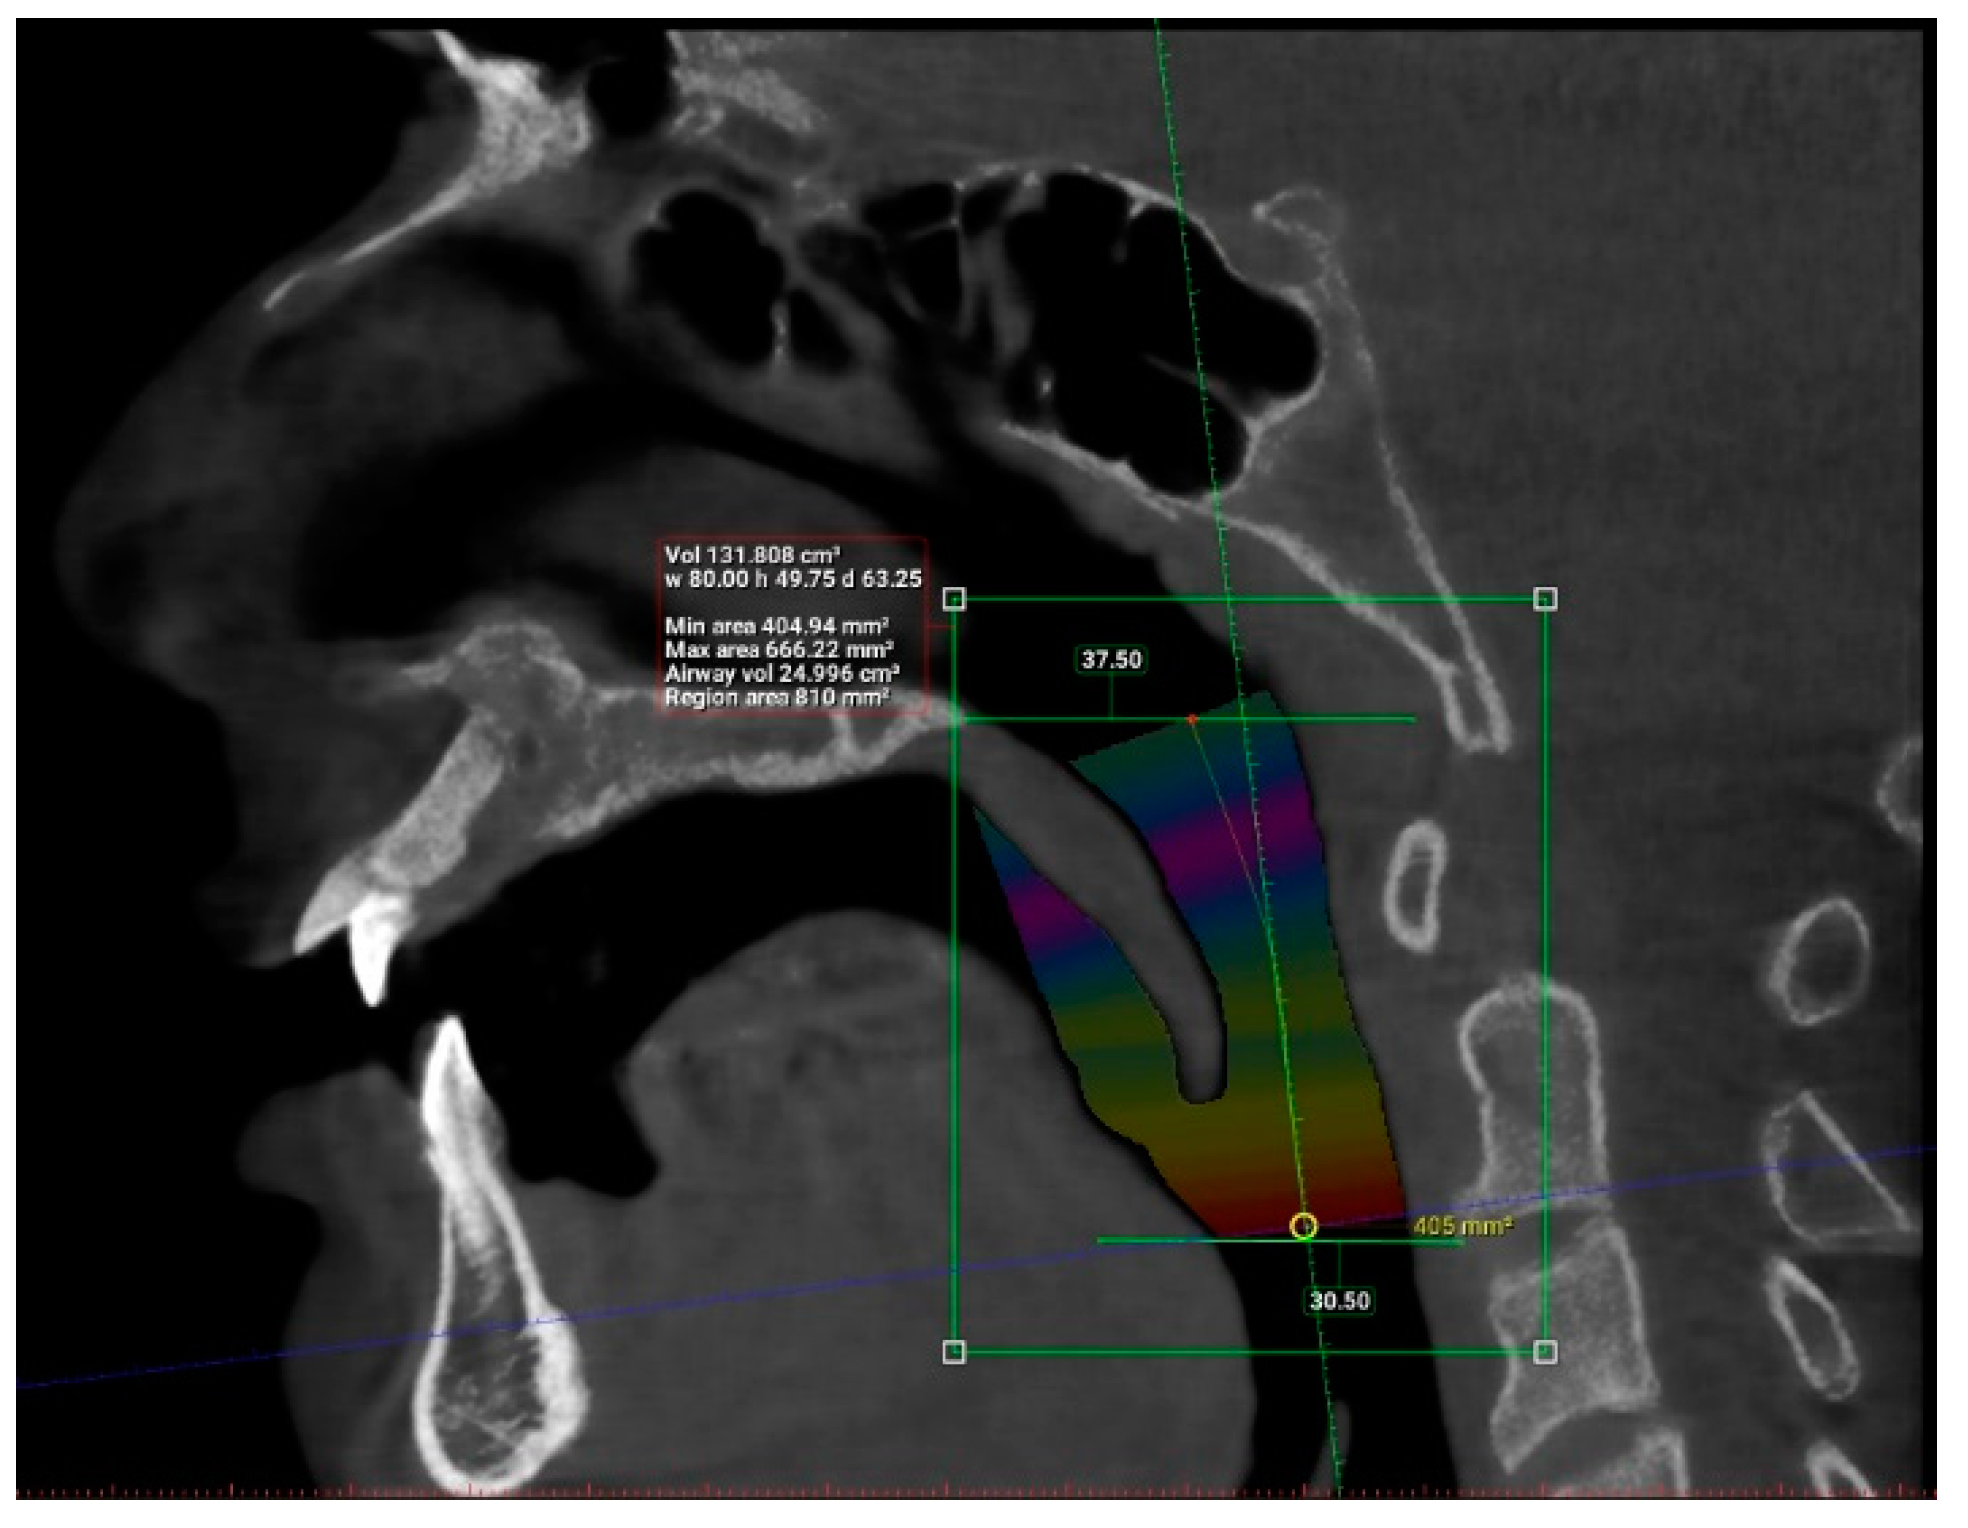

| Length (mm) | 101 | 29.93 | 55.75 | 42.63 | 6.24 |

| Total volume (cm3) | 101 | 94.58 | 173.45 | 131.67 | 17.91 |

| Average volume (cm3) | 101 | 3.34 | 32.09 | 11.10 | 5.21 |

| Antero-posterior (mm) | 101 | 1.00 | 14.50 | 6.44 | 3.19 |

| Width (mm) | 101 | 8.00 | 37.00 | 21.69 | 6.54 |